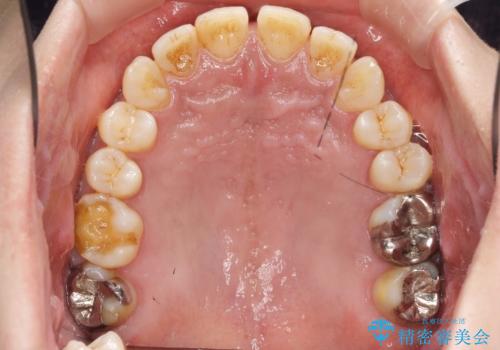

- 笑った時に目立つ銀歯を改善したいとのことで来院されました。

保険適応の銀歯を除去し虫歯を取ったのち、ジルコニアクラウンで置き換えていきます。